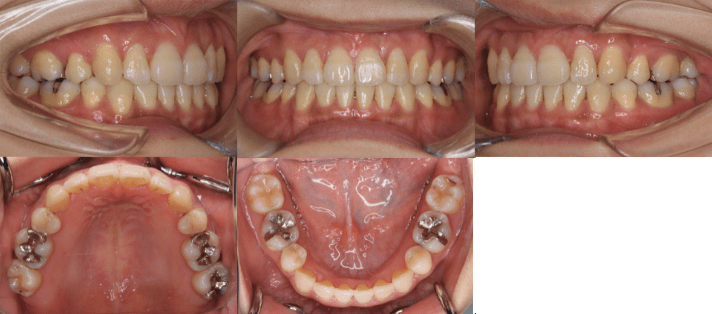

<治療前>

<治療後>

• 初診時年齢:25歳7ヶ月

• 主訴:前歯のガタガタ

• 診断:交叉咬合を伴う叢生症例

• 治療内容:小臼歯4本を抜歯した後、インビザラインを使用して主訴である叢生の改善を行いました。

• 治療期間:2年

• リスク:矯正治療による歯の移動に伴う痛み、歯根吸収、虫歯

• 費用:80万円